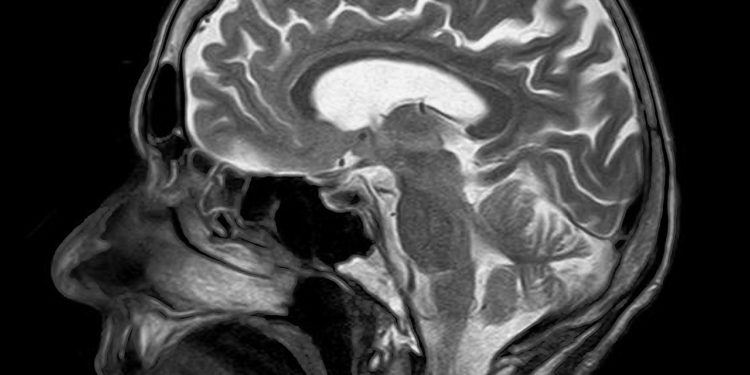

La causa de la ataxia es una alteración genética que puede ser diversa y los que la sufren presentan inestabilidad de la marcha con caídas frecuentes, atrofia del cerebro, falta de coordinación de extremidades superiores, dificultad en el habla y progresivamente algunos pueden precisar una silla de ruedas en fases avanzadas de la enfermedad.